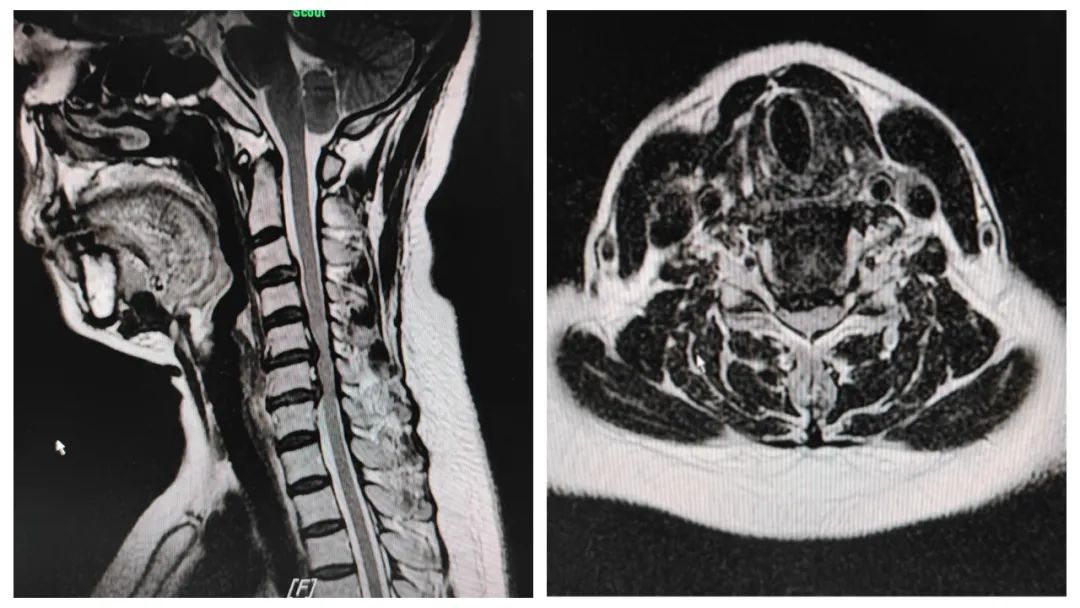

患者王某,女性,50岁,因“颈项部疼痛伴右上肢麻木半年余”入院。入院核磁共振检查示:颈4/5、5/6、6/7椎间盘突出,诊断:神经根型颈椎病。

MRI显示颈4/5、5/6、6/7椎间盘突出